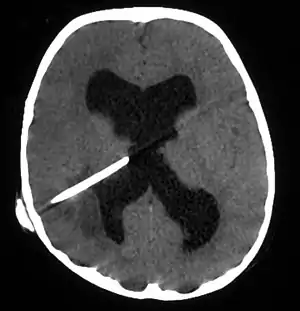

| Brain abscess in a person with a CSF shunt.[1] | |